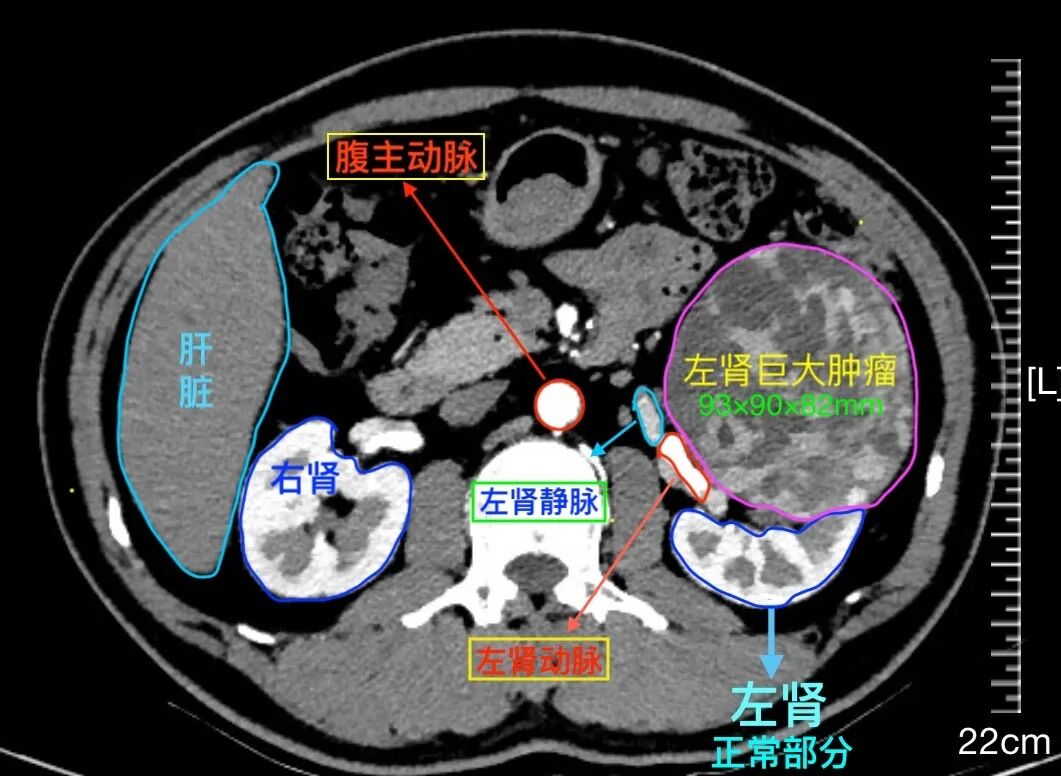

患者文先生在一次常规体检中,意外发现左肾存在一个巨大占位。进一步的增强CT检查结果令人倒吸一口凉气:一个大小约93×82×90mm的类圆形肿瘤从肾脏突出,位置极其凶险,紧贴着肾门部的大血管和集合系统。经专业评估,该肿瘤R.E.N.A.L评分高达11分,属于“高度复杂”级别。